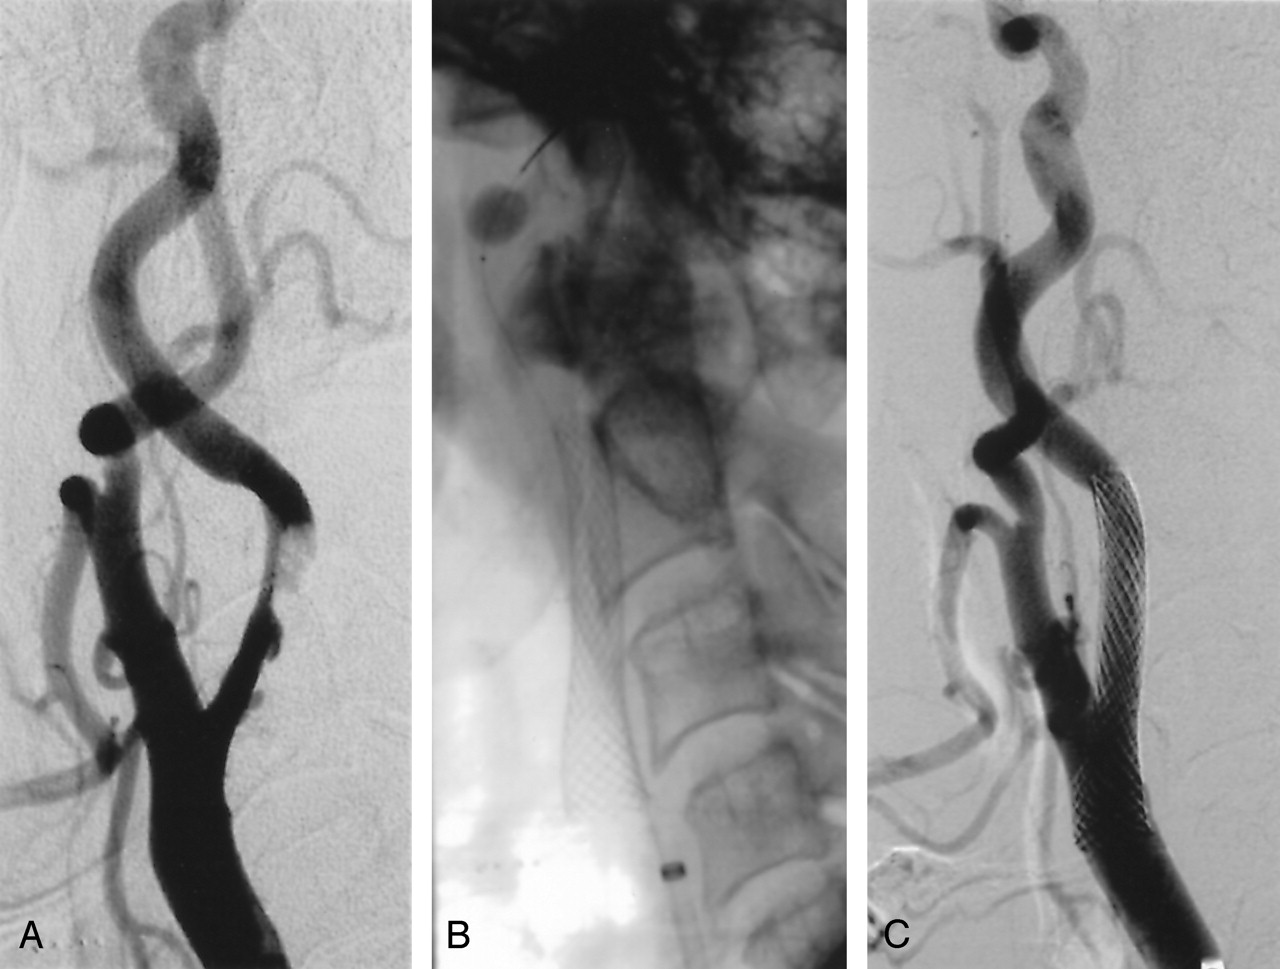

A and B, Illustration of the buddy wire technique in an 82-year-old woman.

A, Left, Left carotid angiogram shows near occlusion of the ICA and significant tortuosity of the distal ICA. Initial attempt to pass the temporary occlusion catheter of the GuardWire protection system through the stenosis was unsuccessful due to the severity of the stenosis. Middle, Angiogram shows a buddy wire positioned through the stenosis and the distal tortuous segment of the ICA. Blood flow through the subocclusive stenosis is hindered by the guidewire with the predilation balloon. Right, Angiogram shows the stenosis predilated with a 3 × 20-mm coronary balloon.

B, Left, Angiogram shows the inflated balloon of the temporary occlusion catheter positioned distal to the stenosis along the buddy wire. Middle, Angiogram shows the postdilated stent. The buddy wire was removed before deployment of the 10 × 24-mm Wallstent. Right, Angiogram obtained after carotid artery stent placement.

In using the buddy wire maneuver, the lesion is first crossed with a properly angulated, highly torqueable 0.014-inch guidewire (eg, Balance; Guidant Inc), which is placed within the distal ICA. A low-profile angioplasty balloon (eg, Ranger, 2 × 40-mm; SciMed Corp) is then advanced into the stenosis and a low-pressure dilation, if needed, is performed. The balloon catheter is then advanced distally into the ICA, and the 0.014-inch guidewire is exchanged for a 0.014-inch extrasupport wire (eg, Stabilizer-Plus; Cordis Inc). This support guidewire straightens the ICA angulations, and through the now partially predilated stenosis and straightened ICA, the temporary occlusion catheter can be advanced into the distal ICA (Fig 3B). If the tortuosity or angulation of the ICA is not severe, the 0.014-inch support guidewire can be withdrawn after placement of the temporary occlusion catheter. Otherwise, the support wire is left in situ, and after predilation with a regular 4 × 40-mm balloon and depending on the configuration of the bifurcation and the cervical segment of the ICA, the buddy wire is a) withdrawn when the stent is in position to be deployed; b) left in situ and removed after the stent is deployed and postdilated (“jailed” buddy wire); or c) left in situ throughout stent deployment, postdilation, application of the Export catheter, and until the temporary occlusion catheter is retracted. The “jailed” support wire is then removed. It should be noted that all of these maneuvers might provoke significant spasm. The spasm typically resolves after all wires are removed from the ICA. In our experience, these maneuvers have never resulted in any vascular damage or increased embolic load (9). The buddy wire strategy not only facilitates the advancement of the temporary occlusion catheter through the stenosis, but also prevents an unpleasant struggle to try to advance and deploy the stent in a tortuous and angulated ICA.